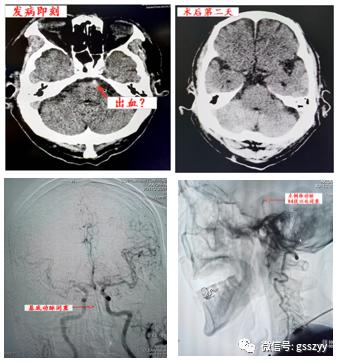

给予患者低分子肝素钙 iH 4000u,bid(每日两次)抗凝治疗。12月4日晚7点,患者因“突发意识不清”转入重症医学科,急请脑病介入科会诊,会诊后判断患者为急性脑血管病,急查颅脑CT提示脑干少量出血(约1mm)。

脑病介入科主任曹骅、心血管病科主任杨宝平仔细查体、阅片后考虑患者病情并非出血引起,而是急性心源性脑栓塞(大脑后循环)所致,且风险极高,少量出血为梗死后出血转化,由于脑干部位出血,为静脉溶栓之禁忌症,因此动脉拉栓成为救治患者的最后一根稻草。

曹骅主任、赵宏廷主治医师于全脑血管造影发现心源性脑栓塞导致左侧椎动脉V3段以远闭塞,明确责任血管后,立即进行拉栓治疗,持续约1.5小时后,成功拉出30mm*15mm一块血栓,3-4mm*4-5mm血栓多块,再次行造影检查发现基底动脉以远血流通畅,患者意识转清,生命体征平稳,取栓成功。